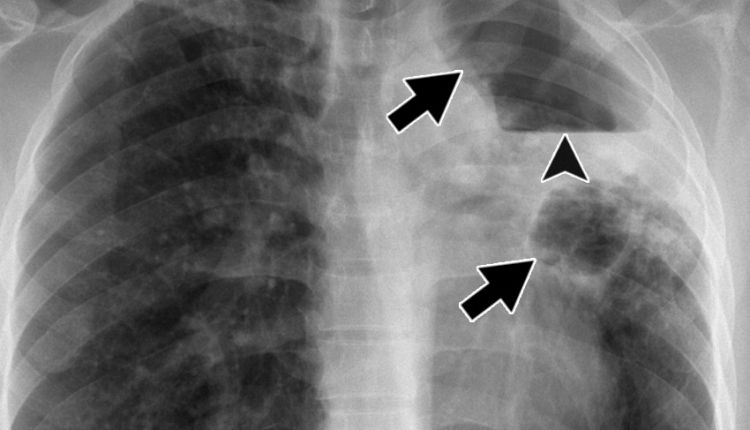

- اختبارات التصوير أو الأشعة السينية على الصدر أو الأشعة المقطعية للبحث عن بقع بيضاء أو تجاويف (تجاويف) في الرئتين ناتجة عن تفاعل مناعي أو تغيرات بسبب المرض